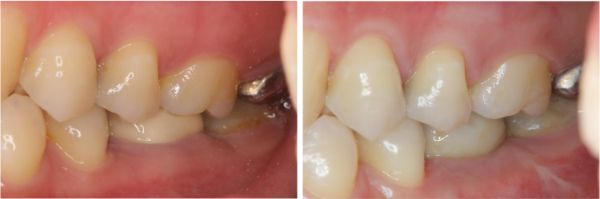

術前、術後比較

使用單顆植牙,不需修磨正常的牙齒,清潔更方便,且咬合更強。